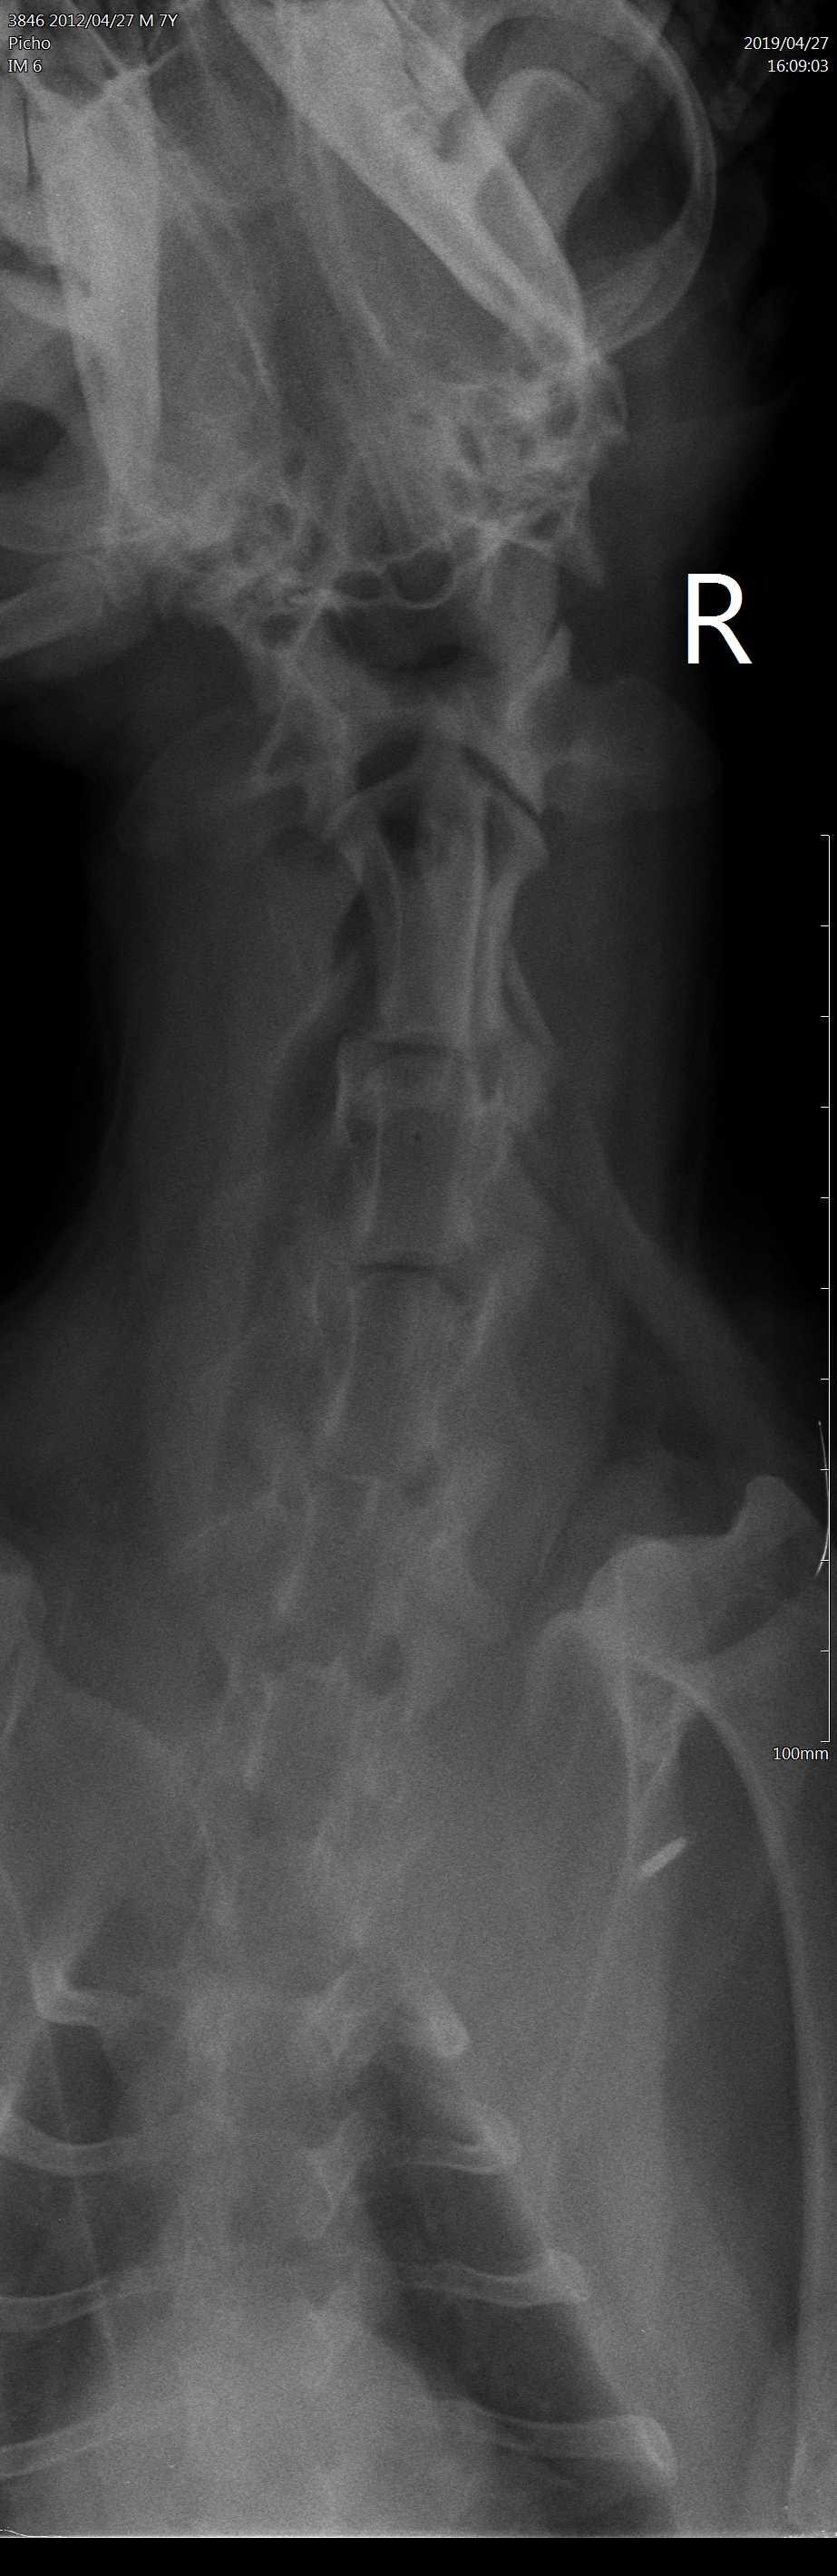

Dears, My dog had a seizure 1 month ago, 2 days ago he was vomiting. Then he was playing with my daughter and she accidentally hit him somewhere in the neck as she says, in the morning we found him paralyzed with all legs he can't walk. We had an X-ray, attached see pics. Our Vet said it could be a tumor he did a surgery, our dog dies 2 days after with tromboembolia sadly. Please advise according to Xray my vet was right or not? Could my daughter caused the tumor?